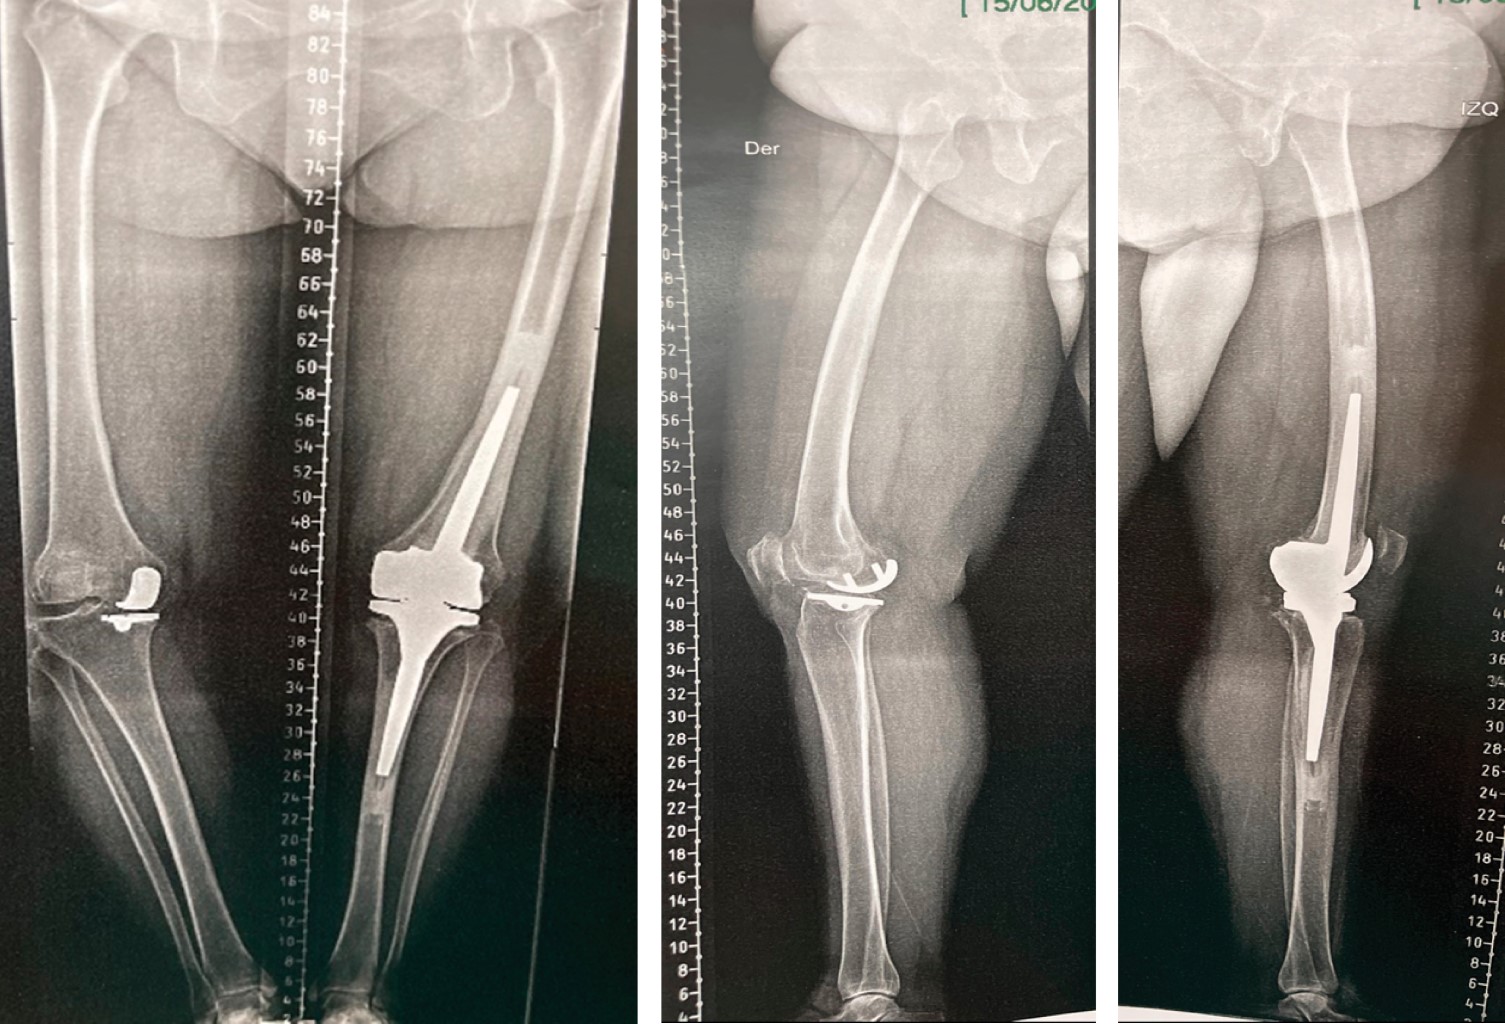

Figure 4

Figure 5

Figure 6